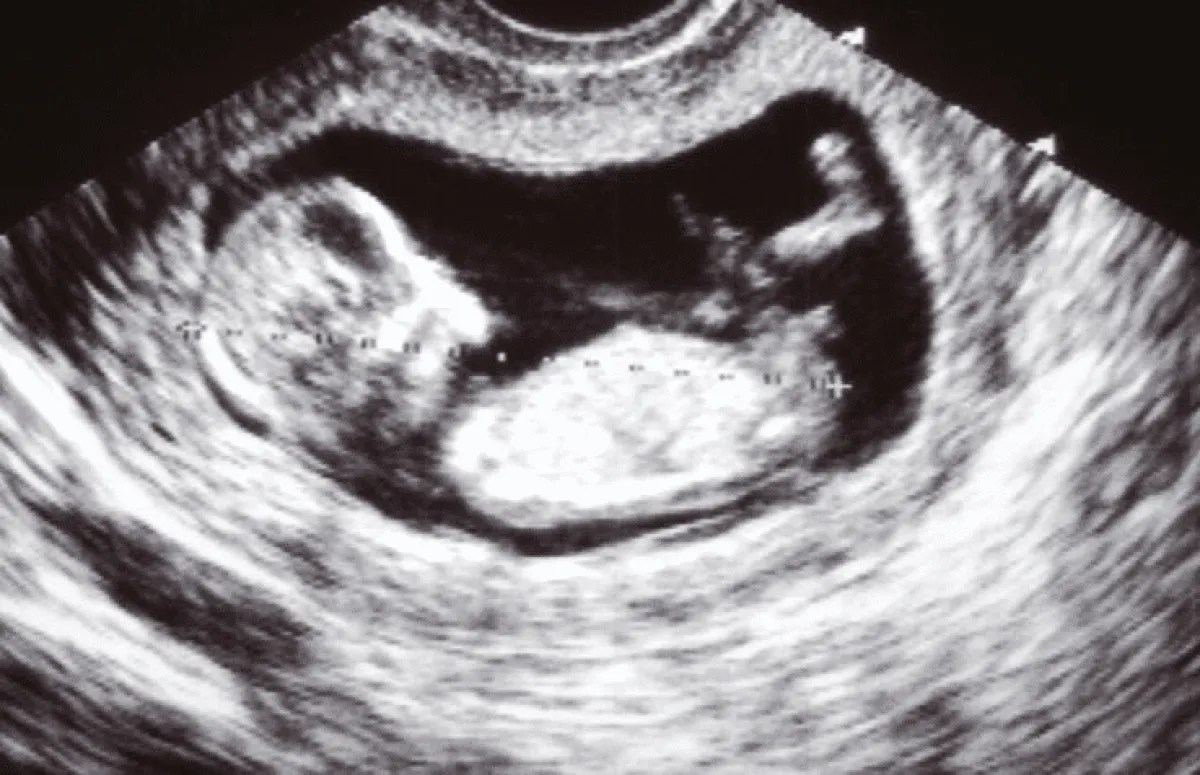

الجنين في الشهر الثالث:

- نظراً لصغر حجم طفلك الصغير أثناء الحمل المبكر، فمن غير المرجح أن تشعري بأي نوع من حركة الجنين في الثلث الأول من الحمل.

- تبدأ الحركات الأولى (المعروفة بالتسريع) في الأثلوث الثاني. في البداية، قد لا تعرف الحامل حتى ما يحدث، لا يزال طفلك صغيراً، لذلك لن تكون الركلات قوية، قد تشعرين بإحساس غريب لا يمكنك وصفه إلا كرفرفة.

- تخيلي سمكة صغيرة تسبح في معدتك (أو أقل قليلاً، حقاً)، وهذا على الأرجح هو ما ستشعرين به، تلك الحركات الأولى، يمكن أن تبدأ في الشهر الثالث من الحمل.